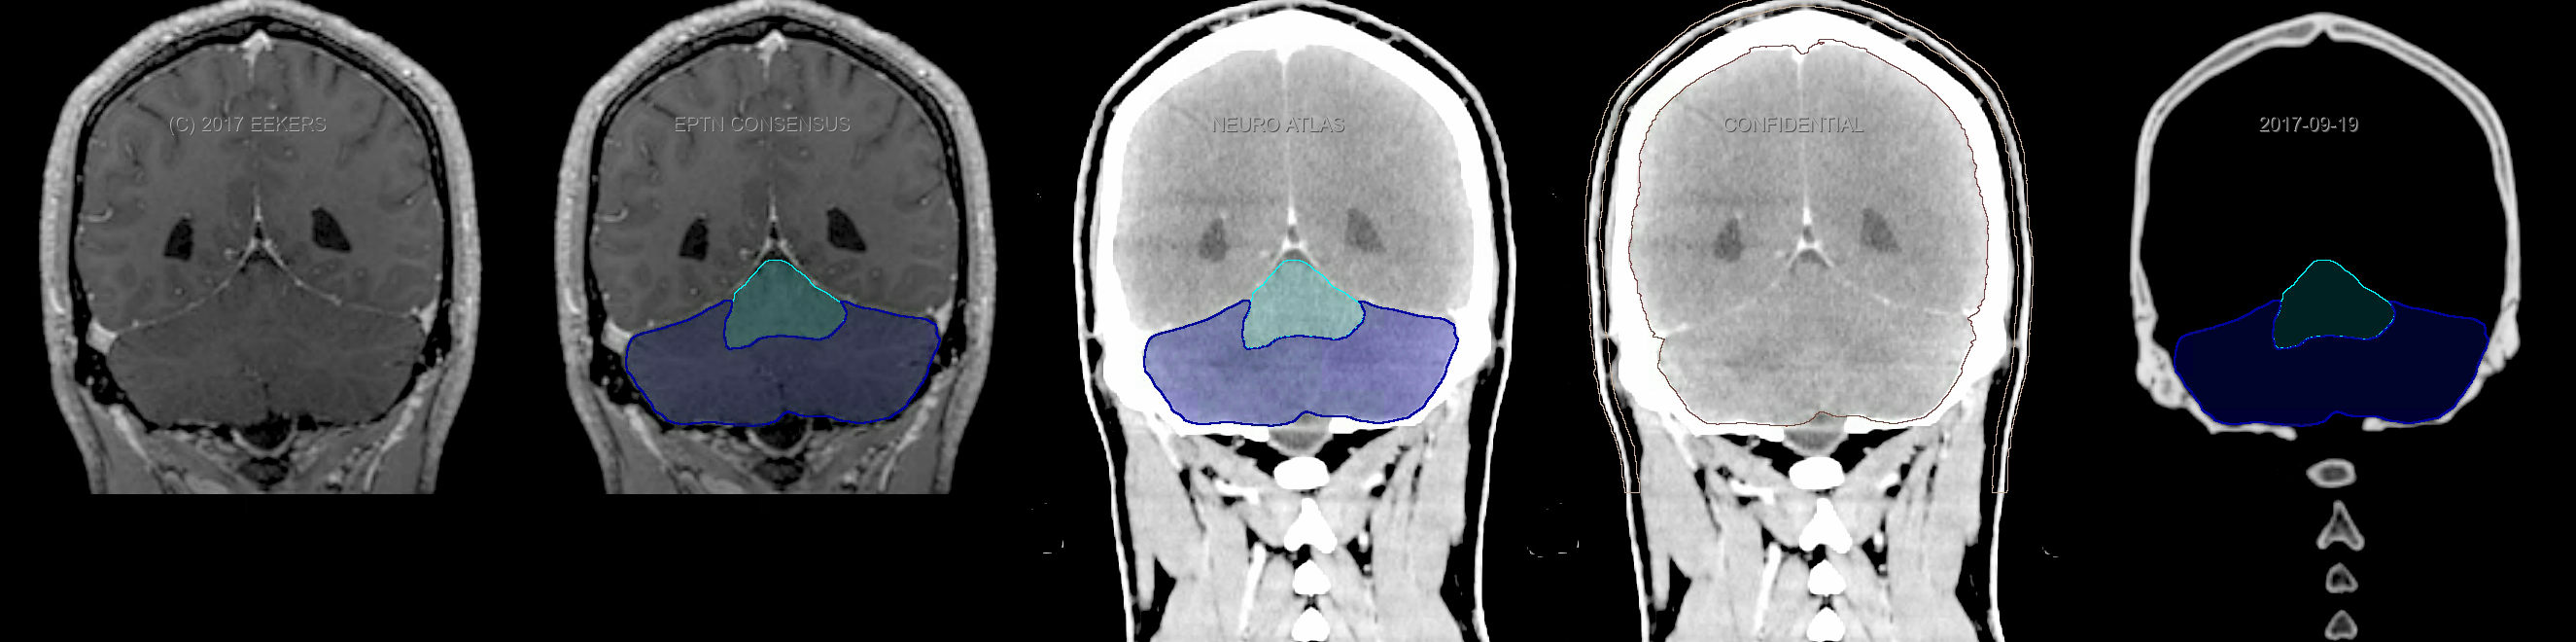

Three-dimensional delineation of the fifteen consensus OARs for neuro-oncology are shown on CT and 3 Tesla (3T) MR images (slice thickness 1 mm with intravenous contrast agent). All are presented in transversal, sagittal and coronal view.

From left to right: MR without structures, MR with structures, CT (WW/WL 120/40) with structures, CT (WW/WL 120/40) with Brain and Brainstem Surface, CT (WW/WL 1500/120)with structures